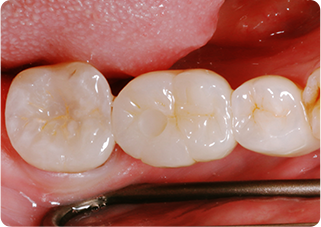

セラミックアンレー症例②

術前

術後

| 主訴 | 右下奥歯の銀歯を白くしたい |

| 治療期間/回数 | 2週間、2回 |

| 価格(税込) | 143,000円(税込) |

| リスク・副作用 | セラミックの破損、一時的な知覚過敏が生じる場合がある |

| ポイント | 銀歯の中はむし歯になっていた。金属イオンにより歯の内部に黒い部分があるが、むし歯を染め出すう蝕検知液を使用し、選択的にむし歯のみを除去。また、セラミック装着時にラバーダム防湿を行うことで、詰め物の接着効果を最大限発揮できるようにした。 |